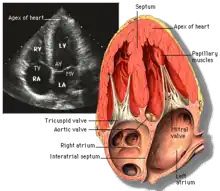

Echocardiography

Echocardiography is regularly utilized to diagnose, manage, and monitor patients with suspected or established heart ailments, making it a highly prevalent diagnostic imaging technique in cardiology due to its speed and efficiency.[3]

Transthoracic echocardiography (TTE)

Transthoracic echocardiography (TTE) uses ultrasonic waves for continuous heart chamber and blood movement visualization. It is the most commonly used imaging tool for diagnosing heart problems, as it allows non-invasive visualization of the heart and the blood flow through the heart, using a technique known as Doppler.